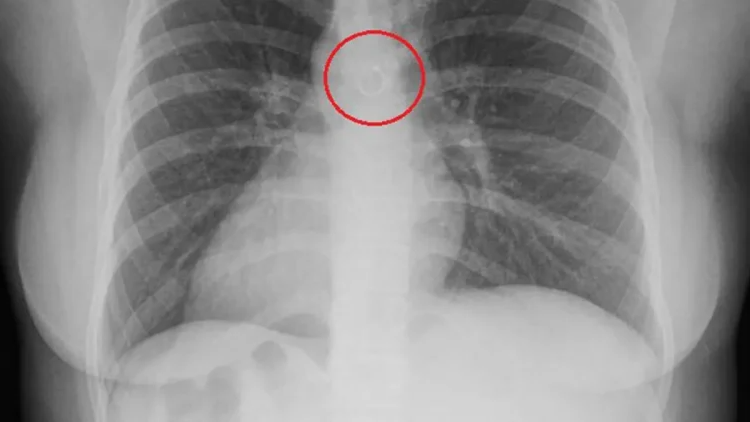

Ситуация оказалась крайне опасной: врачи сообщили, что металлический предмет находился всего в долях миллиметра от аорты. Любое смещение могло привести к тяжёлым последствиям.